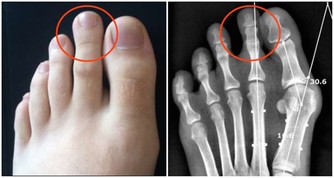

3。吃海鮮時不要喝啤酒

啤酒和海鮮發生反應,會使身體內的尿酸含量迅速升高,對於本身就高尿酸的人來說,容易導致痛風發作。現在,很多三四十歲的中青年人,都有脂肪肝、高血脂、高尿酸等代謝疾病,與不良飲食習慣關係密切。